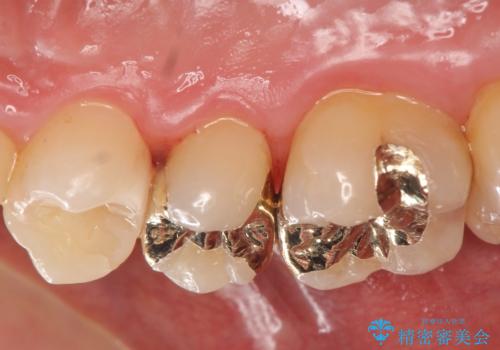

窩洞形態により選択するインレーの素材

虫歯の大きさや残存歯質・窩洞形態によりゴールドやセラミックといった材質を選択することでより歯を削る量を少なくすると同時に強度も確保、長期的な予後を期待できるような治療を実践していきます。

セラミック・ゴールド共に化学的な変化が少なくインレー素材として理想的ですが、色調や強度・加工のしやすさ・最低限必要な厚み等の条件が異なります。